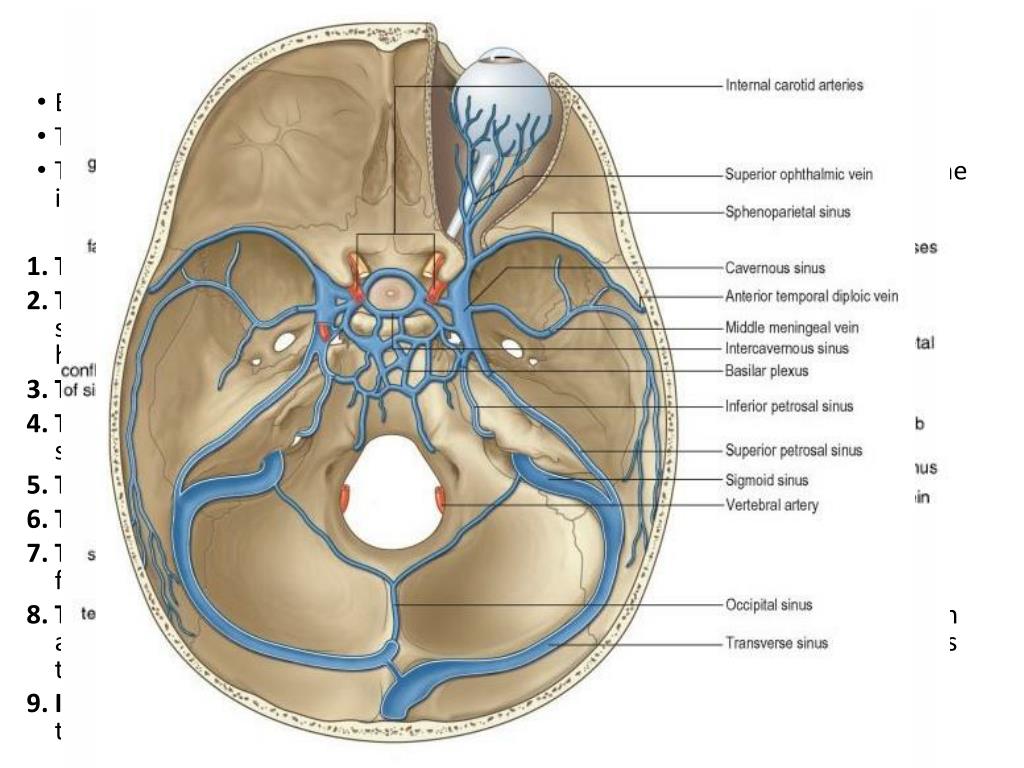

Анатомия внутренней яремной вены: КТ изображения